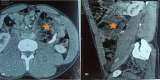

Extra-gonadal mature teratoma: A case report of retroperitoneal location with a literature review

Extra-gonadal mature teratoma is a benign tumor occurring rarely in adults. The retroperitoneal localization constitutes less than 4%. Treatment consists of surgical resection. Histological examination is essential for definitive diagnosis. We reported an unusual case of mature retroperitoneal teratoma discovered in a young man with abdominal pain.